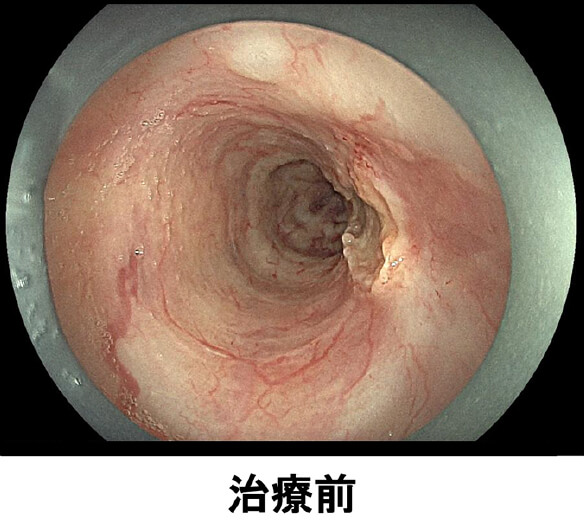

放射線療法後の遺残再発食道癌に対する光線力学的療法(PDT)も行っており、PDTの実施可能施設は九州で4施設のみ、長崎県内では当院が唯一の実施施設となっています。

治療前